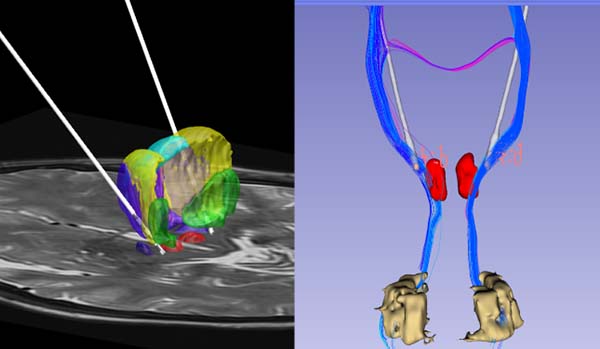

(上左: STN-SNr联合刺激改善帕金森病冻结步态;上右:VIM-PSA联合刺激治疗原发性震颤;下:定量磁敏感成像显示STN)